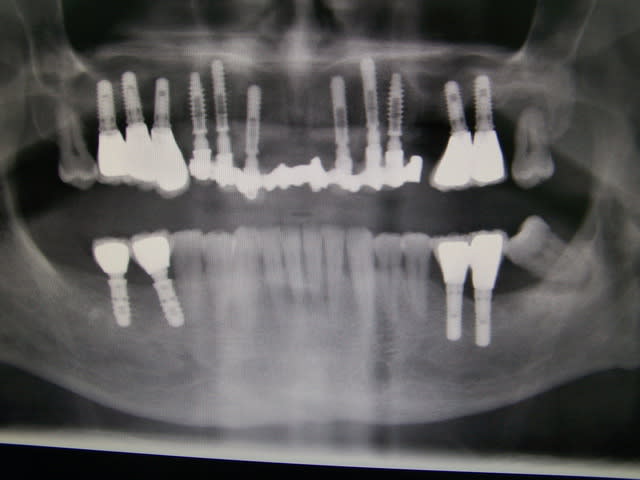

2

cas 1 cool mais ROG à la truelle!

cas 2 l'ex° de la 13 sans casse n'est pas gagné

et es tu certain pour l'implant 8? mettre un 14mm dans une cloison de sinus je ne suis pas pxav